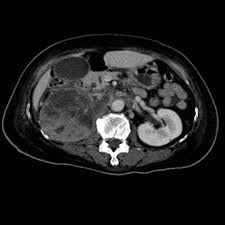

Kidney Tumor On Ct Scan. He also sent me for ct scan to get a clearer view turns out they spotted something on a kidney. Some patients however may need a biopsy.

He also sent me for ct scan to get a clearer view turns out they spotted something on a kidney. Typically these are detected incidentally in other words the patient has a scan for an unrelated problem and a tumor in the kidney is found. It this were indeed a kidney cancer it would be nearly impossible for it to have spread at that size.

Not all growths on. Kidney tumor contained within the kidney small kidney tumor 4cm increasingly we are detecting these small kidney tumors due to the increased use of ultrasound ct scan and mri. It this were indeed a kidney cancer it would be nearly impossible for it to have spread at that size. On imaging they have a variety of radiographic appearances from solid and.